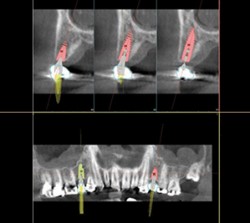

3D Cone Beam Imaging

3D volumes produced with “I-Max Owandy 3D” are used to assess bone quality to implant area and to view all the surrounding anatomic structures

through different planes.100€60€ -

Sinus Lift

A sinus lift is surgery that adds bone to your upper jaw in the area of your molars and premolars. It’s sometimes called a sinus augmentation. Placement of the implants follows after that.

250€200€ -

3D Cone Beam Imaging

3D volumes produced with “I-Max Owandy 3D” are used to assess bone quality to implant area and to view all the surrounding anatomic structures

through different planes.100€60€ -